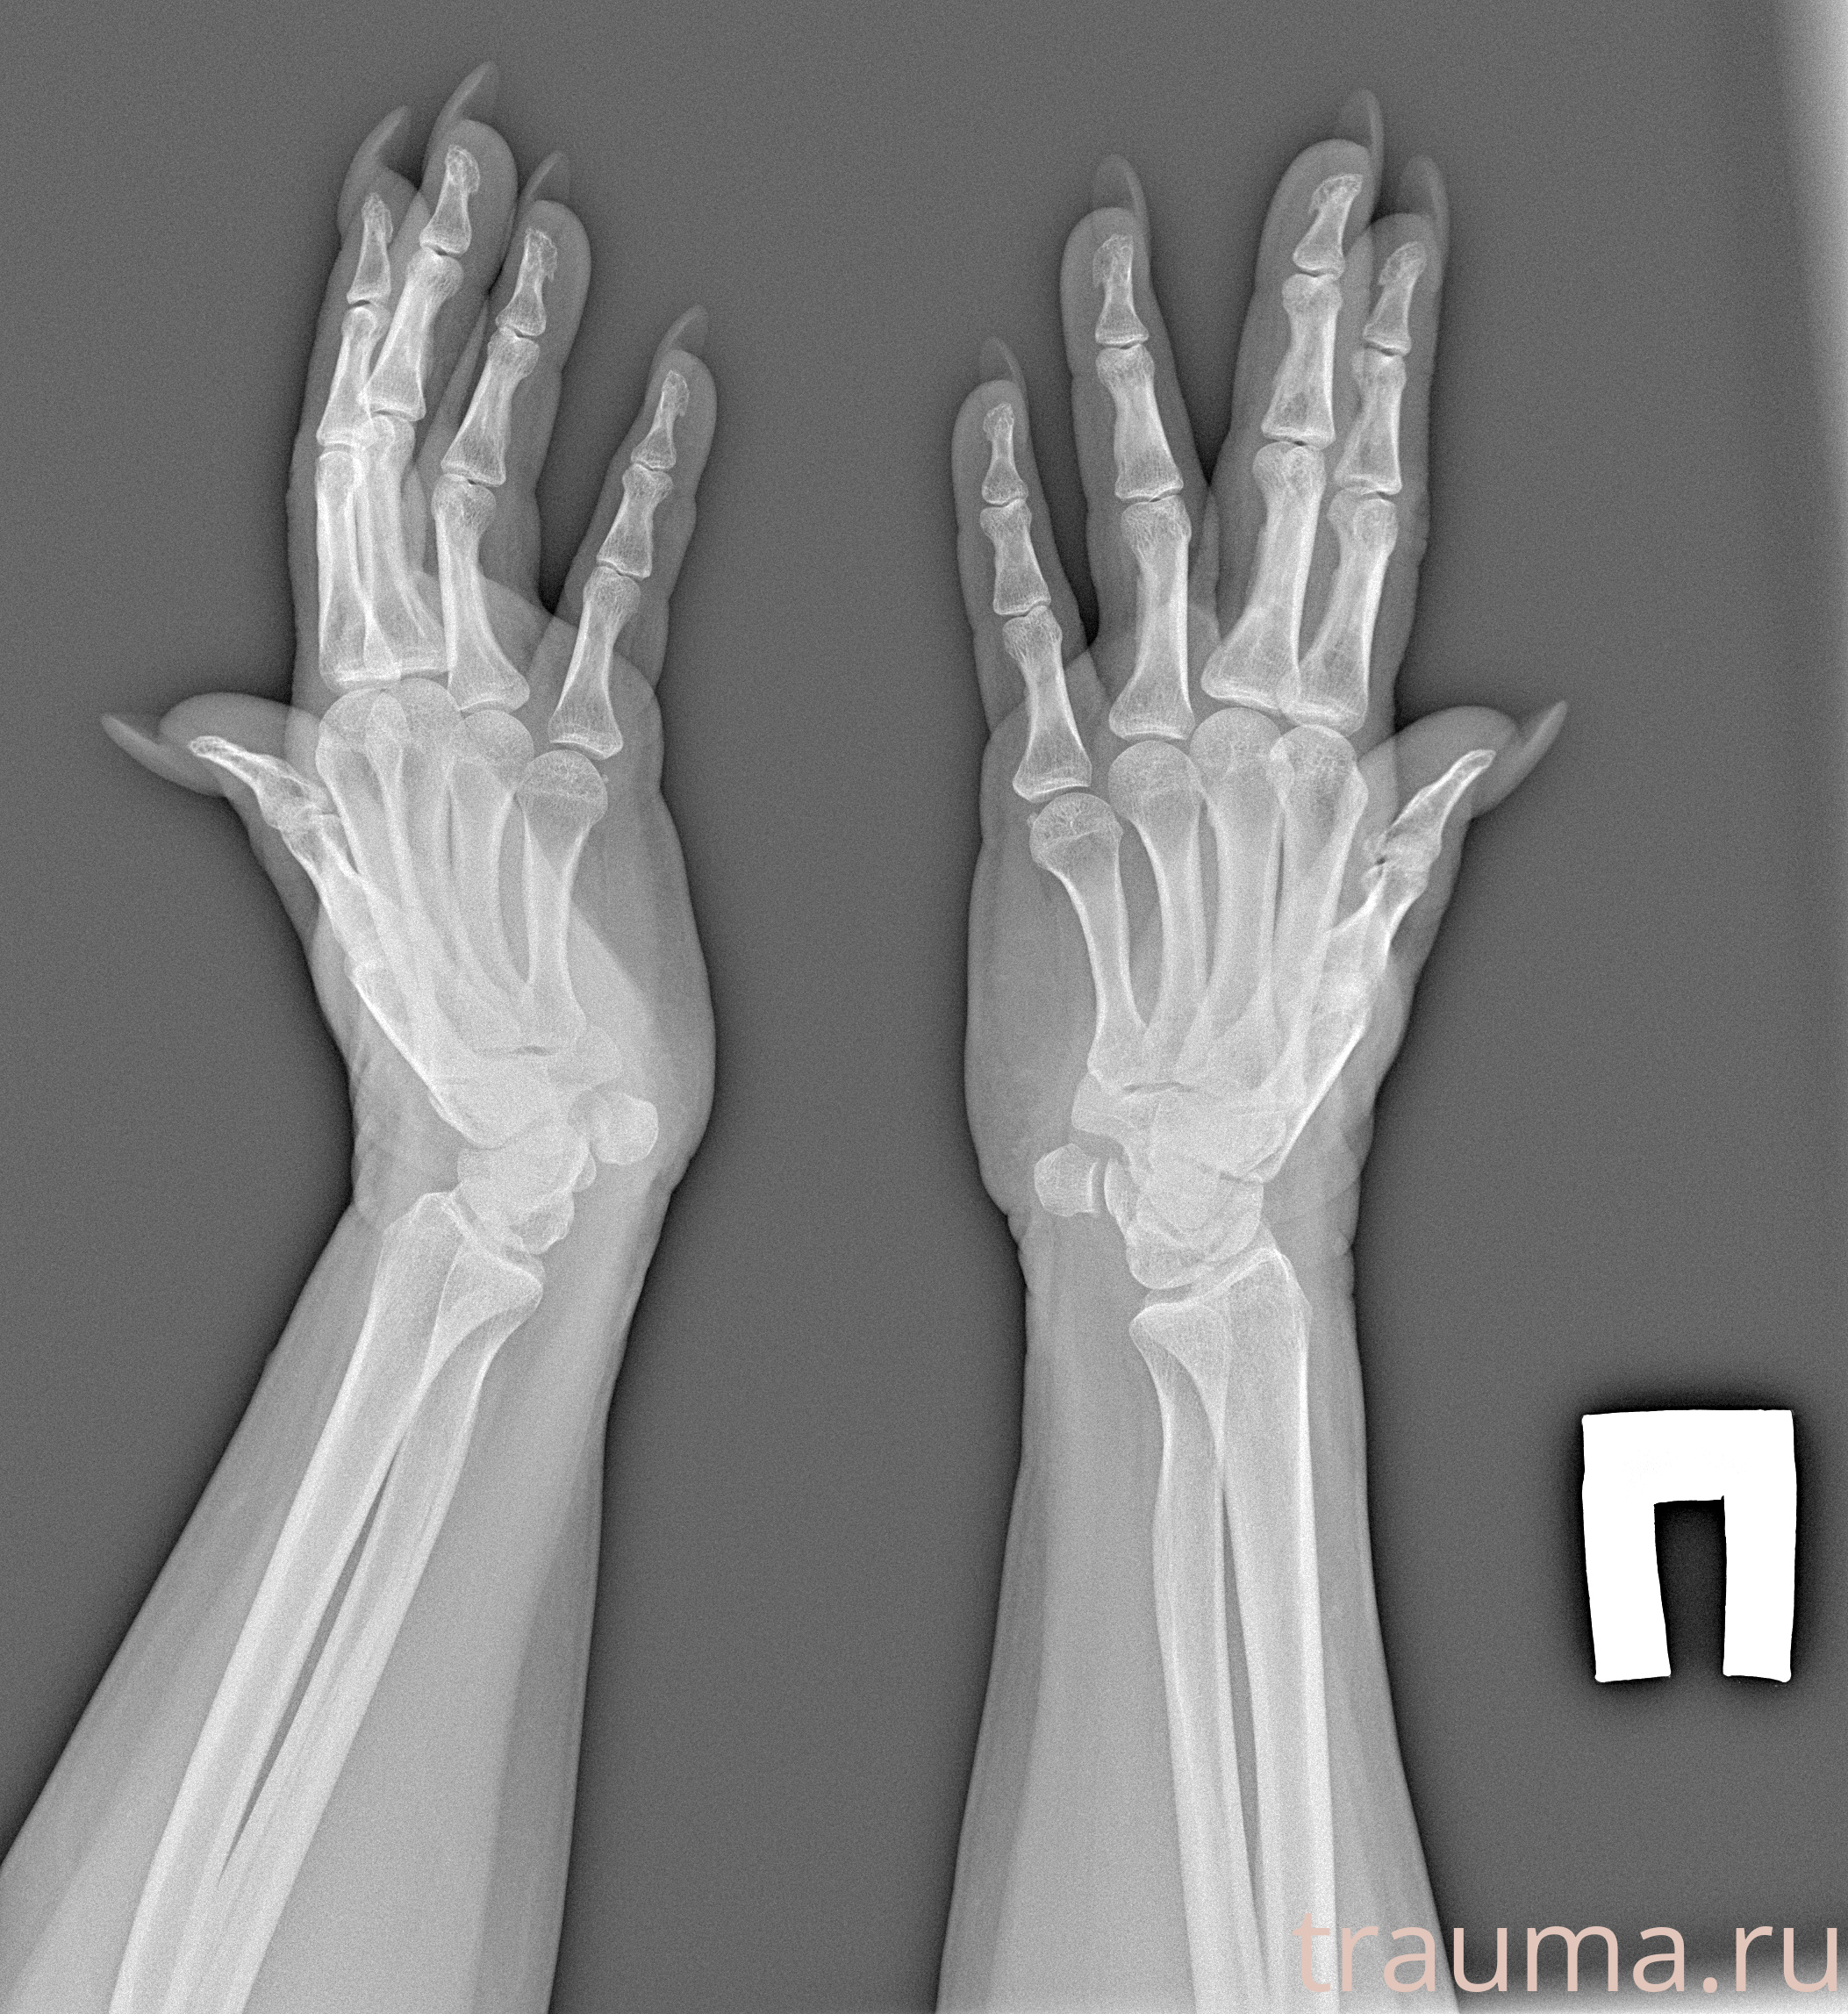

Рентгенограммы

Рентген на дому: по вашему адресу приезжает врач-рентгенолог, травматолог-ортопед с мобильным рентгеновским аппаратом, проводит диагностику травмы или заболевания, делает необходимые рентгенограммы, дает рекомендации по дальнейшему лечению. Получить качественные снимки в домашних условиях возможно благодаря уникальной методике, разработанной МосРентген Центром для института  Склифосовского